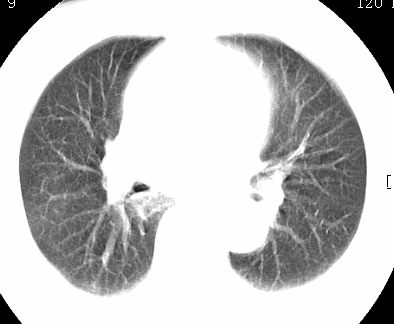

标题: CT26680:肺部右下肺静脉干结节的界定 [打印本页]

标题: CT26680:肺部右下肺静脉干结节的界定

经追查说有支扩咯血病史,但不确定

考虑1、周围型肺癌,2肺静脉畸形,前者可能大,建议增强检查。

不除外淋巴结肿大。

不排除右肺下叶周围型肺癌可能。